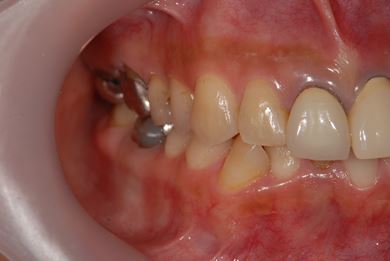

| 性別/年齢 | 女性 / 40歳 | ||||||||||||||||||||||||||||||||

| 主訴 | 前歯のさし歯の部分が目立ってしまい、新しくしたい。痛みも少しある。 | ||||||||||||||||||||||||||||||||

| 治療方針 | 保存不能な歯を抜歯し、セラミック治療にて、機能的・審美的回復を行う。 | ||||||||||||||||||||||||||||||||

| 治療内容 | ジルコニアフレームオールセラミッククラウン7本(オールセラミック用土台3本)、ハイブリッドセラミッククラウン1本、ハイブリッドセラミックインレー1本 | ||||||||||||||||||||||||||||||||